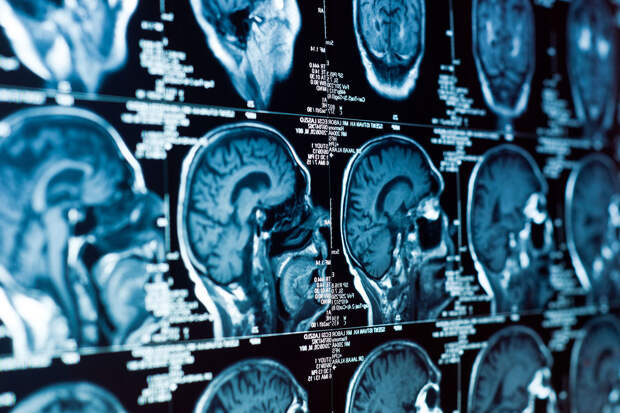

Долговременное снижение калорийности рациона почти на треть может замедлять биологическое старение клеток, обеспечивающих работу белого вещества мозга. К такому выводу пришли ученые из Бостонского университета и Национального института старения США. Работа опубликована в журнале Aging Cell.

Белое вещество — это сеть нервных волокон, покрытых миелином.

За его выработку отвечают олигодендроциты, за иммунный контроль в мозге — микроглия. С возрастом именно эти клетки начинают работать хуже, что приводит к деградации миелиновой оболочки, снижению скорости передачи сигналов и когнитивному замедлению.Чтобы понять, может ли диета повлиять на этот процесс, ученые изучили мозг взрослых макак-резусов, которые более двух десятилетий участвовали в эксперименте по снижению калорийности питания на 30%. Их данные сравнили с животными того же возраста, которые получали обычный рацион.

Ткань из области передней части мозолистого тела — одного из самых насыщенных миелином участков мозга — проанализировали методом одноядерного РНК-секвенирования. Это позволило отследить активные гены в тысячах отдельных клеток.